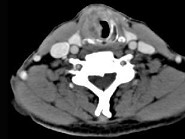

- 单项选择题男,62岁, 声音嘶哑1年余,CT图片如下, 最可能的诊断是 ( )

A、甲状腺癌

B、声门下喉癌伴右颈部淋巴结转移

C、喉结核伴右颈部淋巴结肿大

D、喉转移瘤

E、喉息肉